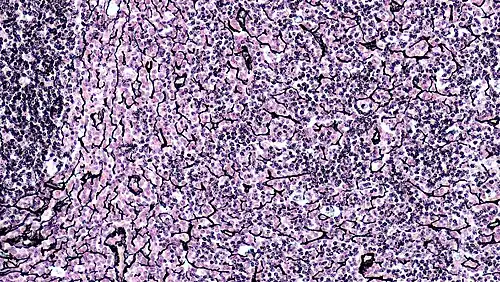

Ретикуля́рная ткань (лат. textus reticularis) — особая форма соединительной ткани[1], состоящая из так называемых ретикулярных волокон и формирующих их ретикулярных клеток. Ретикулярная ткань образует строму кроветворных органов и формирует микроокружение для клеток крови, формирующихся в них[2], однако обнаруживается и в органах, не связанных с кроветворением.

Ретикулярная ткань устроена как трёхмерная сеть, образованная стыкующимися ретикулярными фибробластоподобными[3] клетками, большинство из которых связаны с ретикулярными волокнами и окружают их своей цитоплазмой[4][2]. Благодаря отростчатой форме ретикулярные клетки выполняют механическую функцию. Они также секретируют компоненты основного вещества ретикулярной ткани — преколлаген, гликозаминогликаны, проэластин, микрофибриллярный белок[5].

Ретикулярные волокна достигают 0,5—2 мкм в диаметре и синтезируются ретикулярными клетками. Ретикулярные волокна содержат коллаген III типа и некоторых других типов, гликопротеины и протеогликаны. Они устойчивы к действию слабых кислот и щелочей, а также трипсина. Ретикулярные волокна являются аргирофильными, поскольку они выявляются при импрегнации солями серебра, которыми окрашиваются в чёрный цвет (при окрашивании гематоксилином и эозином они не видны). Аргирофильность ретикулярных волокон обусловлена с высоким содержанием углеводных цепей. К числу аргирофильных волокон также относят преколлагеновые волокна, которые представляют собой начальную форму образования коллагеновых волокон, однако ретикулярные волокна, по сравнению с преколлагеновыми, содержат серу, липиды и углеводы в высокой концентрации. В частности, ретикулярные волокна содержат 6—12 % гексоз против 1 % гексоз в коллагеновых волокнах (в отличие от ретикулярных, коллагеновые волокна содержат коллаген I типа, а не III типа). Ретикулярные волокна также красятся положительно при ШИК-реакции за счёт углеводных цепей, как и при импреграции солями серебра. Из-за малого диаметра ретикулярные волокна при окрашивании сириусом красным и визуализации с помощью поляризационной микроскопии приобретают зелёный цвет[6][7].

Ретикулярные волокна формируют тонкие, рыхло упакованные фибриллы, в которых отдельные волокна связаны друг с другом мостиками, сформированными протеогликанами и гликопротеинами. Фибриллы под электронным микроскопом имеют не всегда хорошо выраженную исчерченность с периодом от 64 до 67 нм. По растяжимости ретикулярные волокна занимают промежуточное положение между коллагеновыми и эластическими[6][7].

Ретикулярные волокна не являются уникальными только для ретикулярной ткани, но именно в ней являются доминирующими[8]. Ретикулярные волокна наиболее многочисленны в гладких мышцах, эндоневрии и строме кроветворных органов (селезёнки, лимфатических узлов, красного костного мозга), в которых они образуют ниши для развития клеток крови. Важную роль в формировании кроветворных ниш играют ретикулярные клетки, которые секретируют факторы роста, необходимые для определённых направлений развития гемопоэтических клеток[5]. Ретикулярные волокна также образуют сеть вокруг клеток некоторых паренхиматозных органов, таких как печень и эндокринные железы. За счет рыхлого расположения и малого диаметра ретикулярные волокна образуют гибкую сеть в органах, которые претерпевают изменение формы и объёма: артерии, селезёнка, печень, матка, мышцы, обеспечивающие перистальтику кишечника[9].